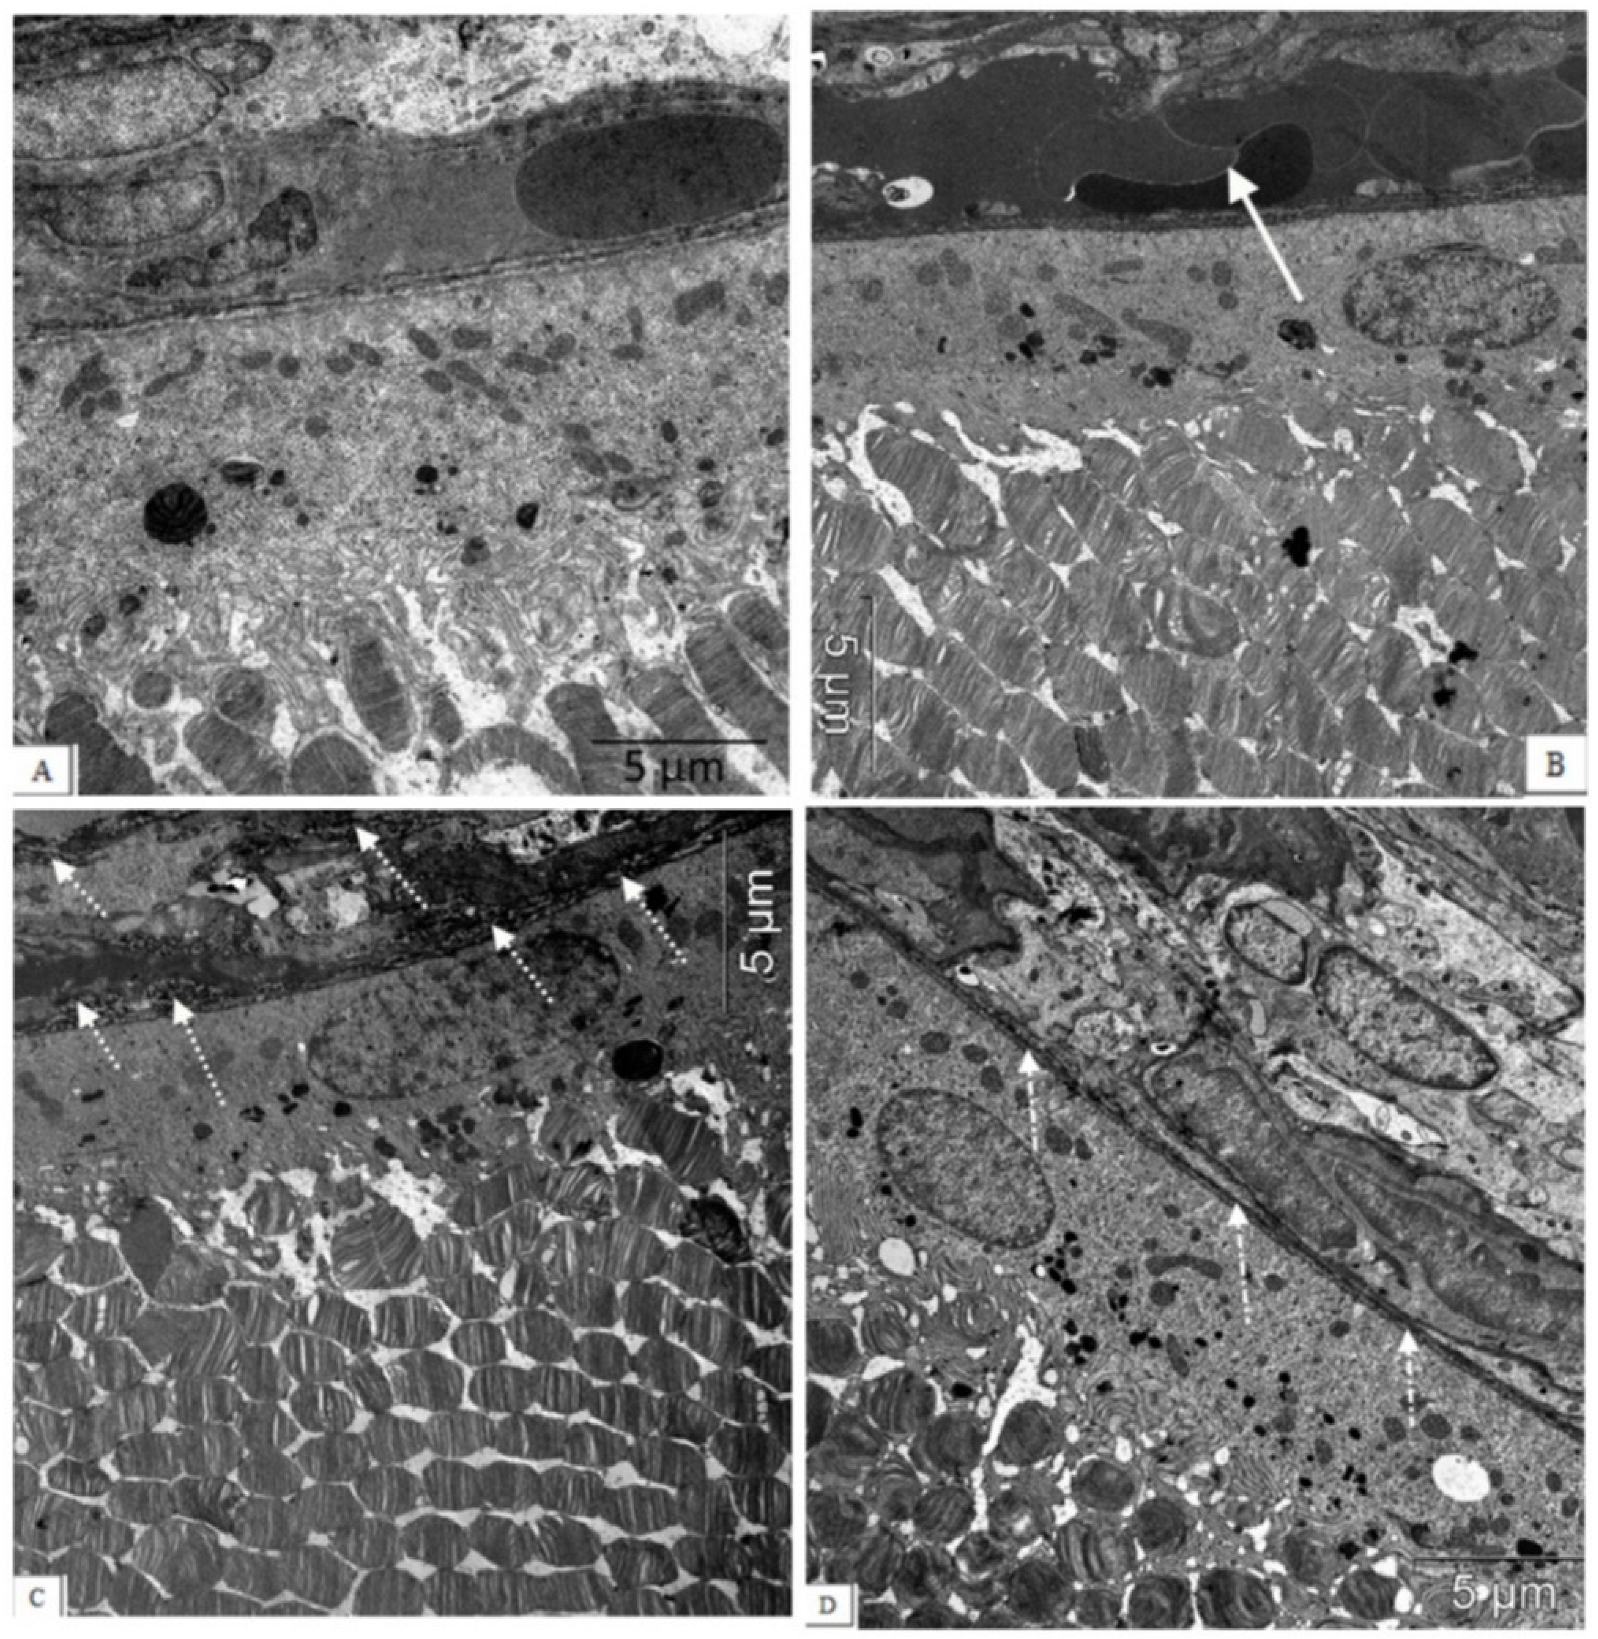

2.5. Electron Microscopic Examination

| Organelles | Type of neurons | Wistar | OXYS | OXYS + IQ-1S |

|---|---|---|---|---|

| Rough ER, % | Associative | 20.41 (17.59; 29.72) | 8.67 (3.89; 8.86) * | 16.22 (12.69; 16.69) + |

| Ganglion | 43.85 (41.17; 59.28) | 13.5 (13.09; 15.69) * | 21.50 (16.24; 26.09) *+ | |

| Mitochondria, % | Associative | 16.29 (16.13; 16.66) | 3.51 (3.19; 3.79) * | 9.23 (7.02; 14.43) *+ |

| Ganglion | 16.98 (16.72; 17.49) | 3.55 (2.26; 5.21) * | 7.41 (6.53; 7.80) *+ | |

| Golgi apparatus, % | Associative | 1.26 (1.18; 1.39) | 0.64 (0.53; 0.83) | 1.75 (1.16; 2.06) |

| Ganglion | 1.86 (1.43; 2.93) | 1.66 (0.79; 1.77) | 1.41 (1.09; 2.92) | |

| Lysosomes, % | Associative | 0.49 (0.35; 0.73) | 0.31 (0.27; 0.37) | 0.39 (0.02; 0.77) |

| Ganglion | 0.58 (0.55; 1.02) | 0.56 (0.27; 0.80) | 0.64 (0.02; 1.39) | |

| Vacuoles, % | Associative | 0.08 (0.06; 0.1) | 2.40 (1.73; 2.4) * | 1.00 (0.8; 1.09) *+ |

| Ganglion | 0.19 (0.04; 0.36) | 3.18 (2.37; 3.4) * | 1.12 (0.98; 1.16) *+ |